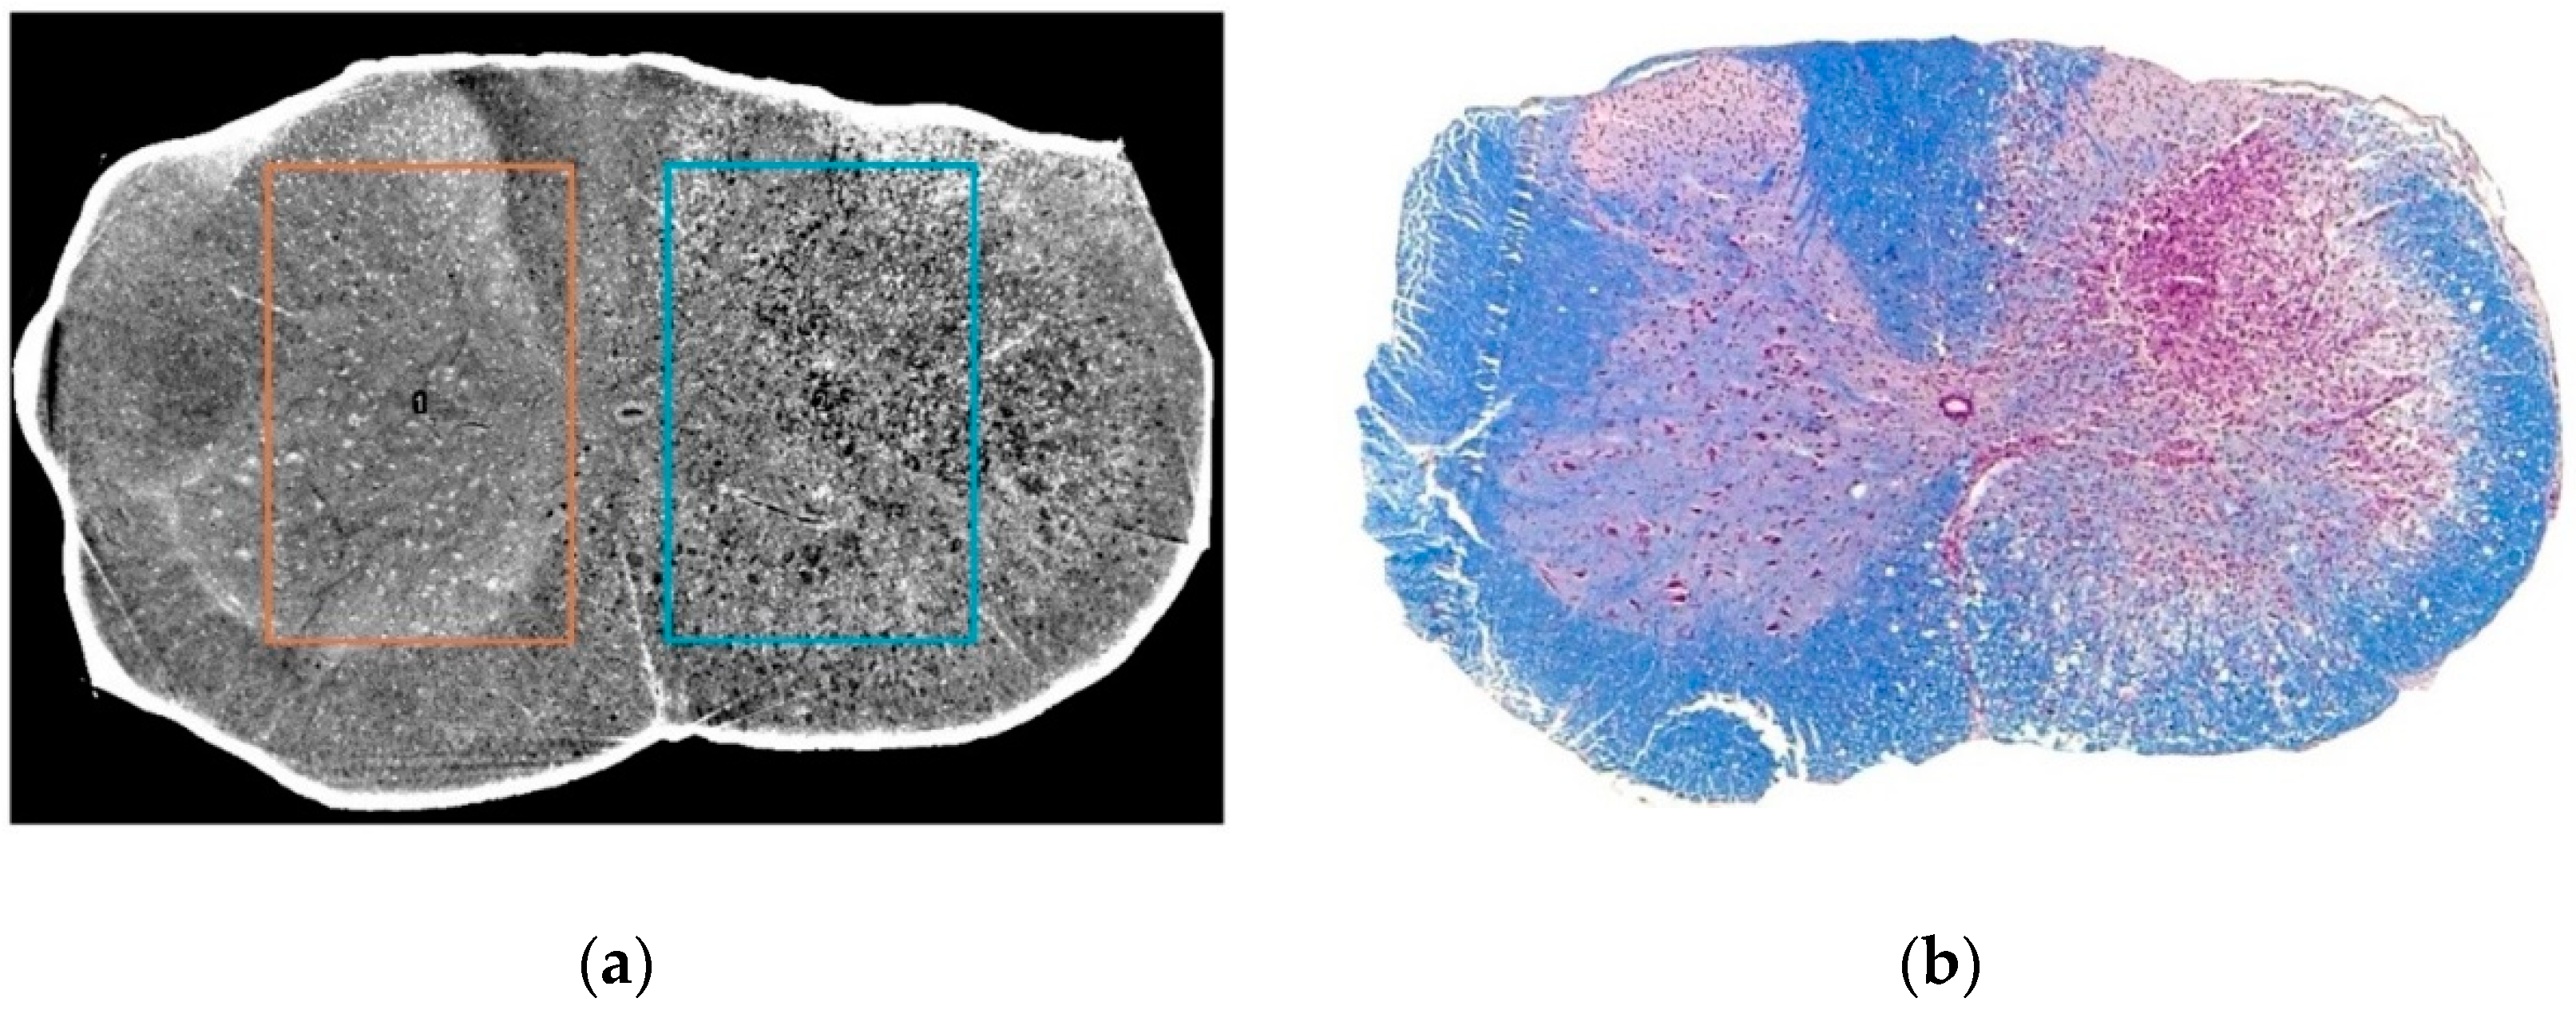

- Fratini, M.; Bukreeva, I.; Campi, G.; Brun, F.; Tromba, G.; Modregger, P.; Bucci, D.; Battaglia, G.; Spanò, R.; Mastrogiacomo, M.; et al. Simultaneous submicrometric 3D imaging of the micro-vascular network and the neuronal system in a mouse spinal cord. Sci. Rep. 2015, 5, 8514. [Google Scholar] [CrossRef] [PubMed]

- Cedola, A.; Bravin, A.; Bukreeva, I.; Fratini, M.; Pacureanu, A.; Mittone, A.; Massimi, L.; Cloetens, P.; Coan, P.; Campi, G.; et al. X-Ray Phase Contrast Tomography Reveals Early Vascular Alterations and Neuronal Loss in a Multiple Sclerosis Model. Sci. Rep. 2017, 7, 5890. [Google Scholar] [CrossRef]